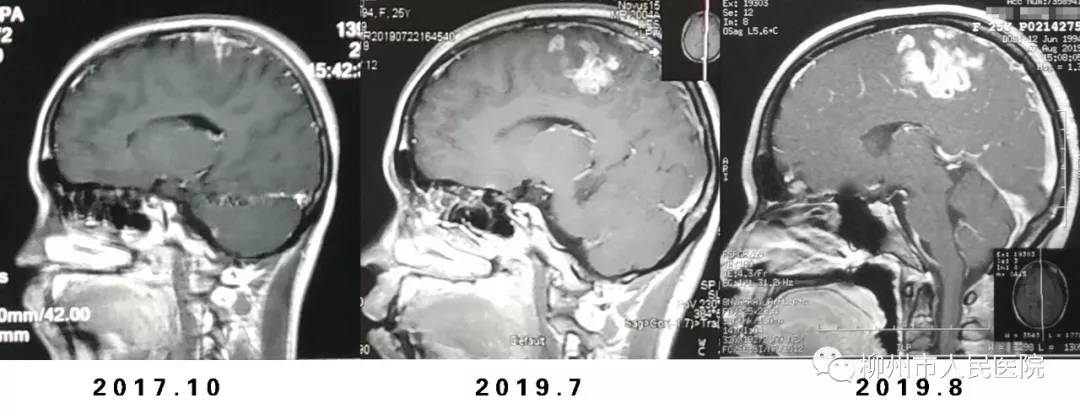

家住柳州市郊区的芳芳今年25岁,正当花季,可她在2年前右侧肢体开始出现反复抽搐,到当地医院就诊时发现她的脑部有一个米粒大小的病灶,结合既往她有外伤病史,当时诊断为脑内软化灶、继发性癫痫,仅服用抗癫痫药物治疗,未做其它处理。

近段时间以来,芳芳右侧肢体抽搐的频率明显增加,还伴有右侧肢体乏力的现象。今年7月底,她在柳州市某医院做了磁共振检查发现脑部病变有所增大,诊断为寄生虫(裂头蚴)感染,需手术治疗,但考虑到手术风险很大,芳芳一直没有下定决心做手术。

▲芳芳的脑部病变逐渐增大。